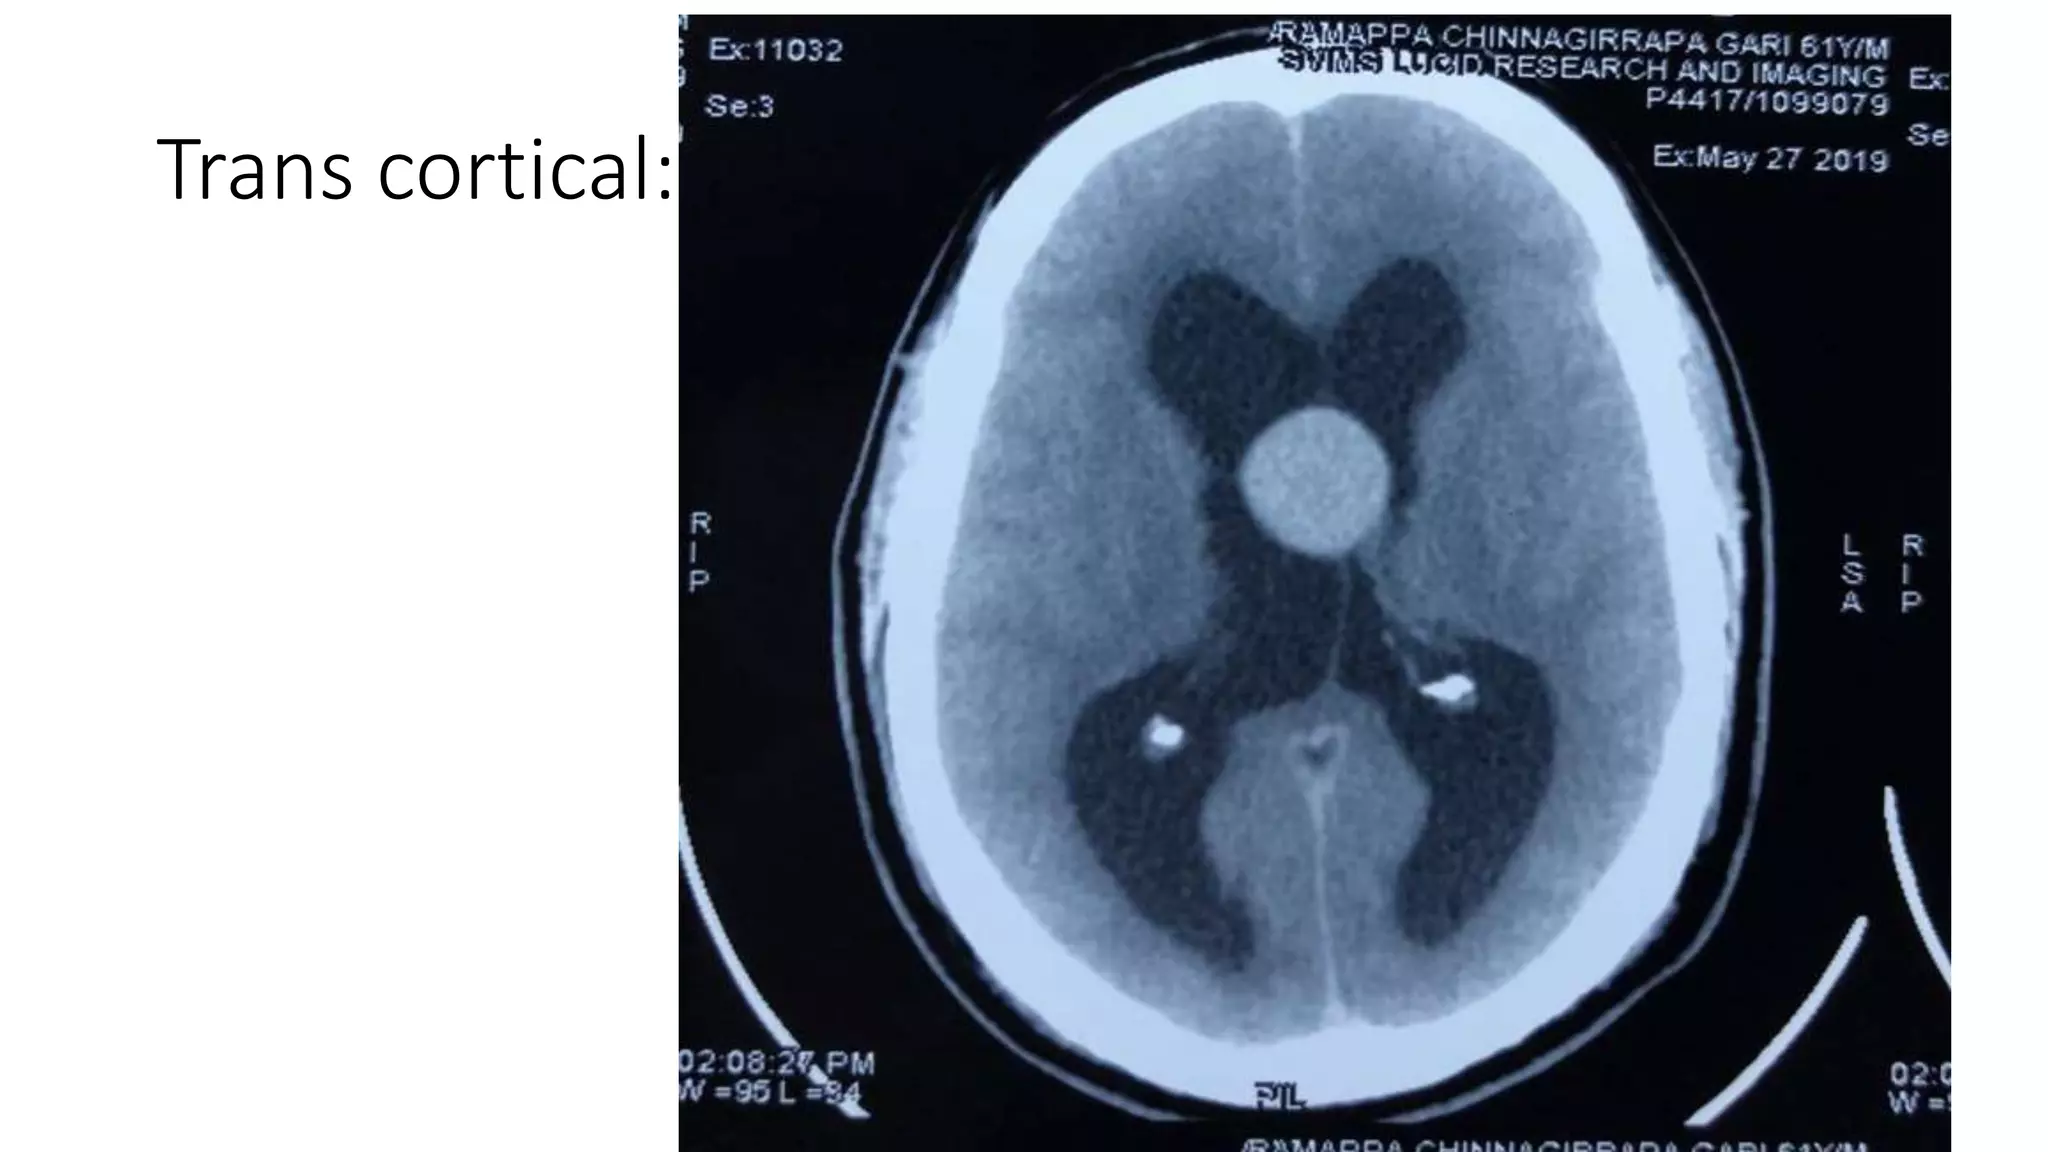

Trans cortical

Trans cortical:

• 19 patients underwent trans cortical approach